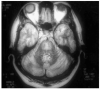

Fig. 1. Corte axial de la resonancia magnética cerebral, con un área de hiperintensidad en la protuberancia sugestiva de mielinolisis central pontina (T2).

Fig. 2. Corte sagital de la resonancia magnética cerebral. Hipointensidad en la base de la protuberancia (T1).